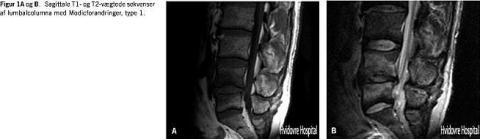

Modic-forandringer, dvs. knoglemarvsforandringer under de vertebrale endeplader, blev beskrevet af de Roos i 1987 og klassificeret af Modic i 1988 [36, 37]. Forandringerne menes at være forbundet med diskusdegeneration, men det er vigtigt at understrege, at der ikke foreligger signifikante sammenhænge mellem disse forandringer og klinisk patientstatus. Hypotetisk forekommer en diffusion af inflammatoriske mediatorer fra diskus gennem fissurer i endepladerne til knoglemarven som følge af repetitive mikrotraumer af diskus. Modic type I (lavt signal på T1/højt signal på T2)-forandringer er histologisk karakteriseret ved transformation af knoglemarv til fibrøst, neovaskulariseret væv (Figur 1A og B ). Type I-forandringerne menes at signalere tidlige og aktive forandringer. Type I-forandringer transformeres undertiden til den mere stabile type II-forandring (højt signal på T1/isodenst eller forøget signal på T2), og sjældnere til type 3-forandringer (lavt T1/lavt T2). Forandringerne ses hos 20-50% af LRS-patienterne, men der er ikke opgivet prævalenser hos asymptomatiske individer [5, 38]. Relevansen af Modic-forandringer på MR-skanning for graden af degeneration, symptomatologi eller prognose er altså uafklaret.